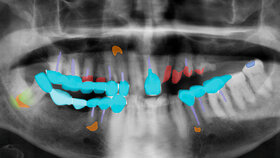

Künstliche Intelligenz (KI) wird künftig auch eine bedeutende Rolle in der Zahnmedizin spielen. Noch ist die Technik jedoch mit vielen Unwägbarkeiten behaftet.